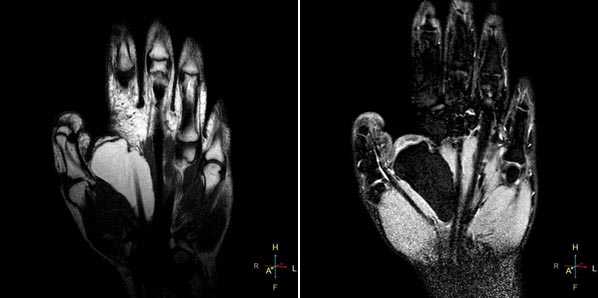

Начнем с МР-диагностики травматических повреждений кисти и лучезапястного сустава.

При клиническом обследовании больных с ушибами лучезапястного сустава и кисти, как правило, определяются болезненность при пальпации, увеличение объема окружающих мягких тканей, а объективно и рентгенологически изменения отсутствуют. Наиболее часто встречаются ушибы метаэпифиза лучевой и локтевой костей, а также полулунной и ладьевидной костей. Ушибы (контузионные поражения) кисти определяются только при МРТ-исследовании, особенно хорошо видно на программах с подавлением сигнала от жира. Морфологически ушиб кости проявляется нарушением целостности трабекул костной ткани с кровоизлиянием и отеком костного мозга. Однако, несмотря на повреждение трабекул костной ткани, рентгенологические исследования, включая КТ, не позволяют обнаружить патологические изменения.